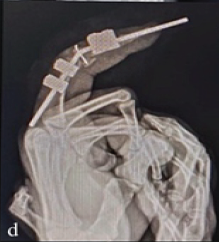

Arthroscopic-Assisted Removal of Incarcerated Fragment following Manual Reduction of Posterior Hip Dislocation in Acute Polytrauma Patient: A Case Report